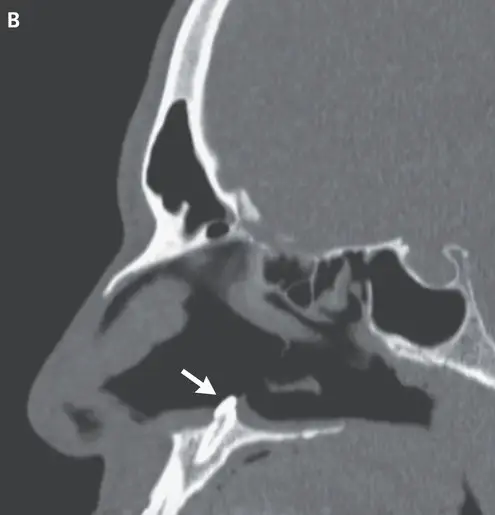

"Computed tomography of the paranasal sinuses showed a well-defined, radiodense mass consistent with an inverted ectopic tooth in the nasal cavity (Panel B, arrow), which was thought to explain the obstructive symptoms and septal perforation.

"The tooth was removed during oral and otolaryngologic surgery by means of an intranasal approach and measured 14 mm in length. There were no postoperative complications.

"At follow-up three months after surgery, the patient’s symptoms of nasal obstruction had resolved."